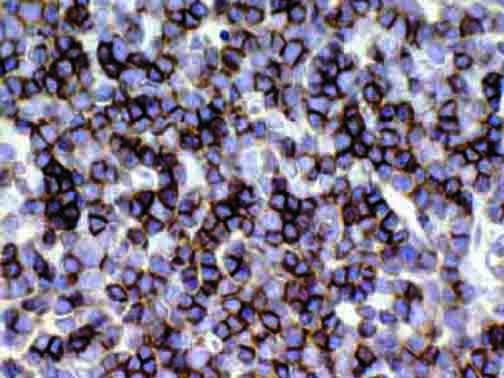

It is the ICU physician who is most likely to witness one of the deadliest manifestations of the abnormal immunological response, the cytokine storm syndrome (CSS). This response is also referred to by some as the cytokine release syndrome (CRS). CSS is characterized by continuous activation and expansion of macrophage and lymphocyte populations, which secrete large amounts of cytokines, causing the cytokine storm. This massive cytokine release is akin to hemophagocytic lymphohistiocytosis (HLH) disease, a syndrome characterized by initial unchecked and persistent activation of cytotoxic T lymphocytes and NK cells.